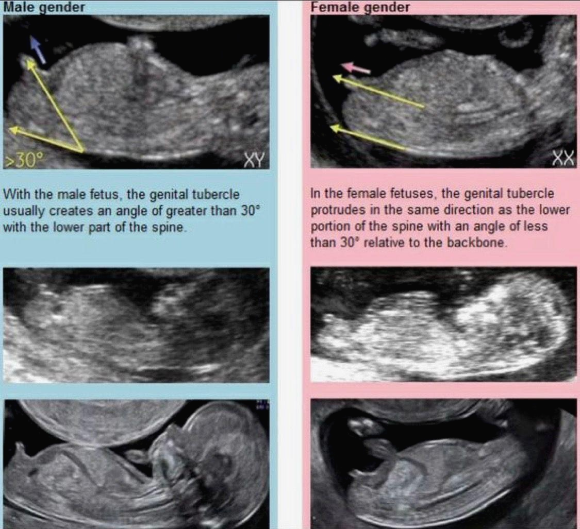

각도법은 태아의 성기를 관찰하여 성별을 예측하는 방법입니다. 이 방법은 임신 12주 이상의 초음파 검사와 함께 사용됩니다. 태아의 생식기가 척추와 얼마나 각도를 이루고 있는지를 확인하여 성별을 구분하죠.

남아와 여아의 초음파 이미지를 비교하여 각도가 어떻게 다른지를 설명하고 있습니다. 남아는 30도 이상의 각도를 보이고 여아는 30도 이하의 각도를 보입니다. 남아와 여아의 초음파 이미지를 통해 각도 차이를 명확하게 보여주고 있습니다.